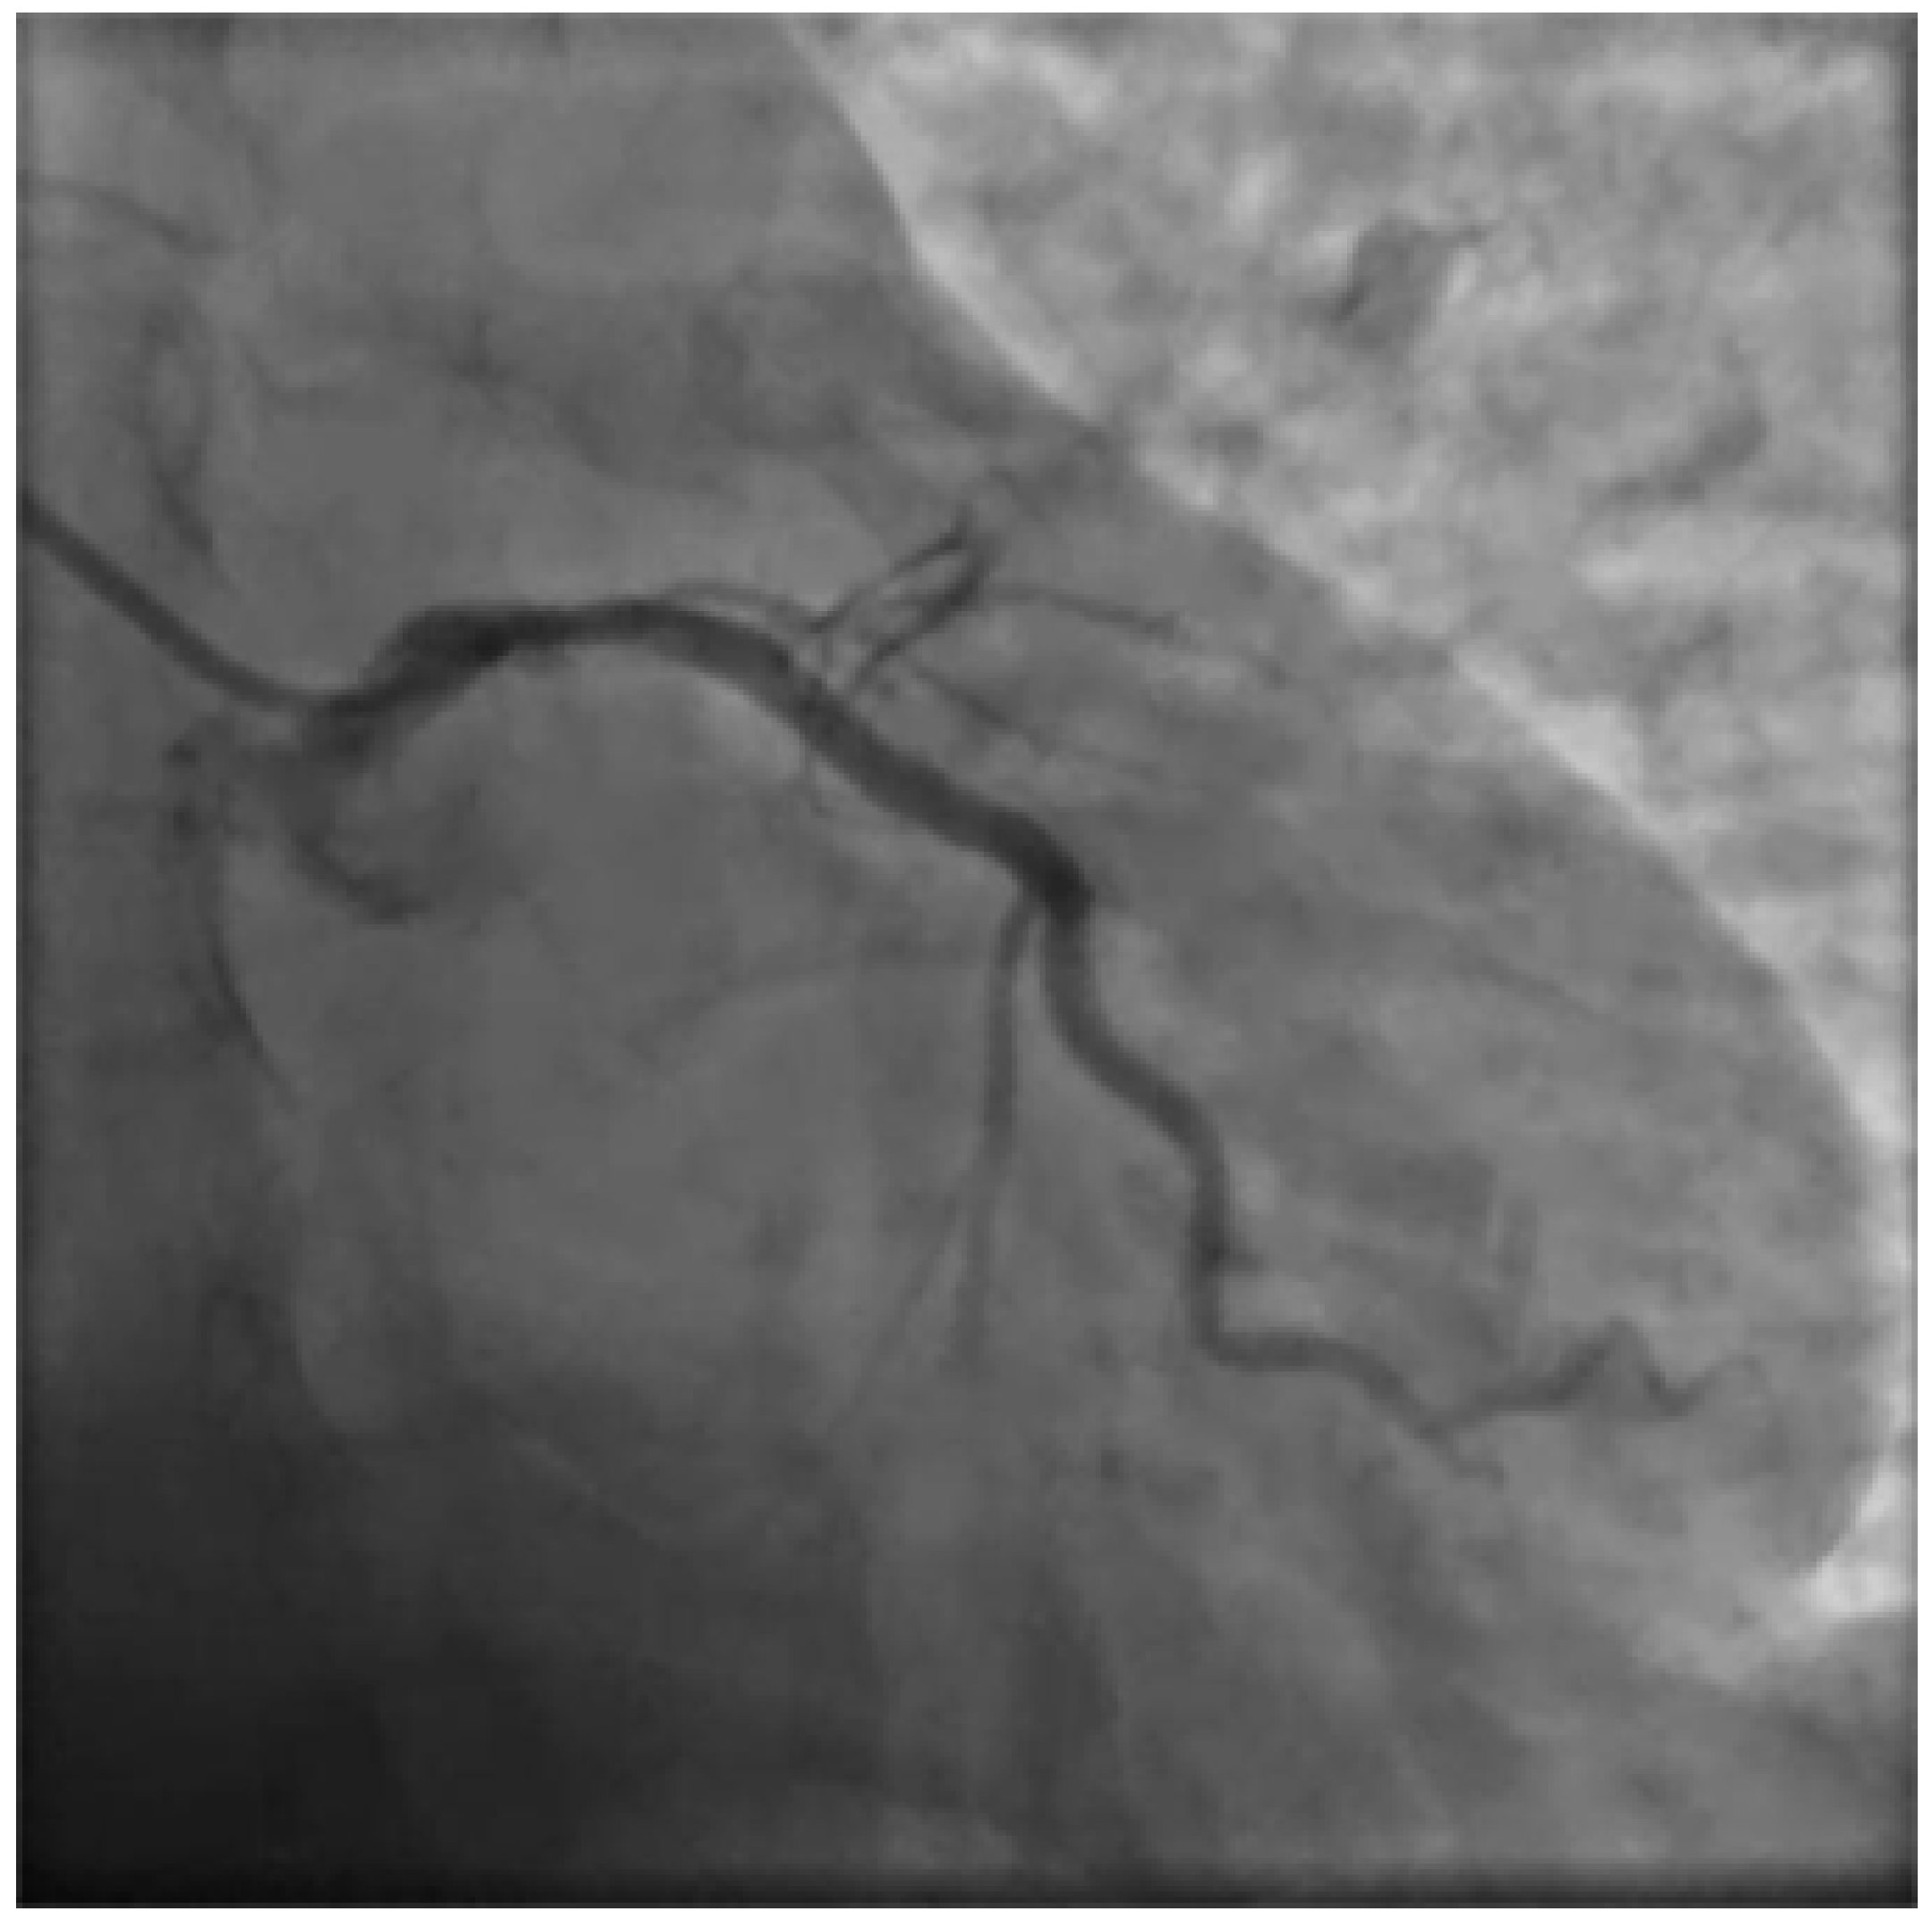

Due to the unusual setting involving a 36 weeks pregnant woman several other specialists were involved in the care process setting up an emergency pregnancy heart team involving cardiologists, gynecologists, anesthesiologists, pediatricians and the radiology specialist. Emergency bed side echocardiogram showed significant left ventricular compromise with an estimated ejection fraction of 30-35% with anterior, lateral and apical akinesia. Due to the unstable and acute condition of the woman a decision was quickly made to proceed with an emergency coronary angiography and PCI. A rapid response gynecology team followed the procedure ready to intervene promptly in case of maternal deterioration with unresponsive cardiac arrest. Full anticoagulation was achieved with 7000 IU of unfractioned heparin. A 6F left radial access was obtained, aiming to be as coaxial as possible, and the left coronary artery angiogram was obtained with a standard 6F JL 3.5 catheter showing LM dissection involving the ostial LAD which showed complete occlusion with TIMI 0 flow.

Figure 2. Basal PA caudal projection.